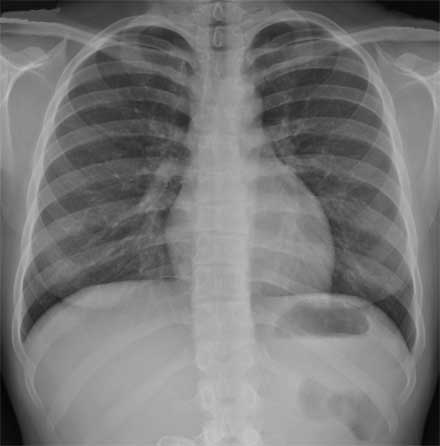

Radiografía posterior/anterior del pecho en una mujer normal.

Nota: Las imágenes se muestra para fines ilustrativos. No trate de sacar conclusiones comparando esta imagen con otras en el sitio. Solamente los radiólogos calificados deben interpretar las imágenes.